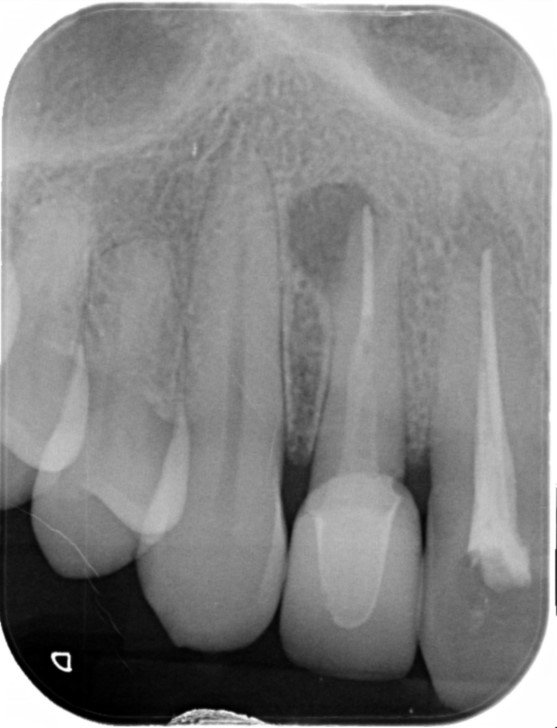

Case

60代女性

10/23

ひびが入っている根っこがあることがわかります。

12/3

ひびが入っていた根っこ以外を利用してできるだけ抜歯を避けました。

10/15

見た目も違和感なく被せ物をかぶせることができました。

治療部位 | 右下6番 |

---|---|

費用 | 約100000円 |

治療期間 | 9ヶ月 |

注意事項(リスク・副作用など) | 当院では抜歯と他院で言われてしまった歯もできるだけ残せるように最善を尽くすよう努めております。 |

カテゴリ | 歯内療法 |

他院で作成された被せ物をやり替えた際にお痛みがあり、再度治療を始めたがこれ以上の治療はできないと言われてしまい治療中断。

悩まれた末に当院にご来院くださりお話をお聞きしました。

1つの根っこにひびが入っていることなどがわかりましたが抜歯ではなく、できるだけ歯を残存させることを目的とした治療計画を立てて根っこの治療を開始しました。